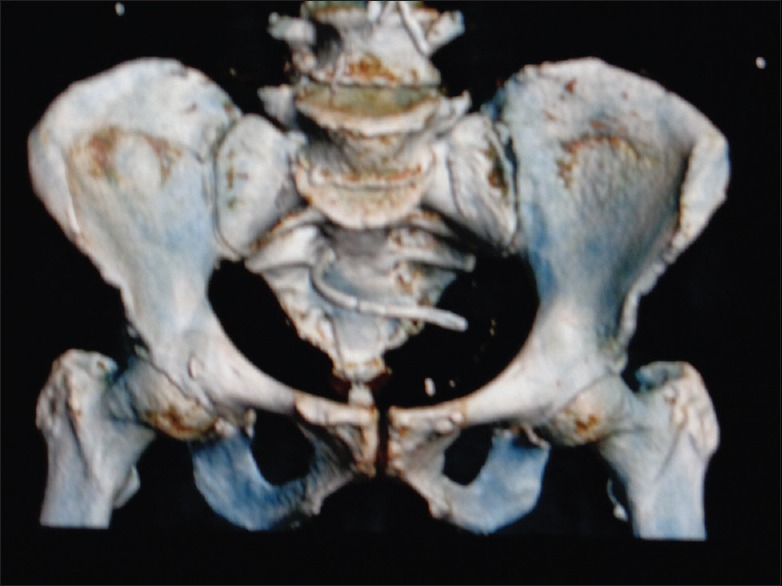

The common bile duct stenting has been a common endoscopic procedure practiced worldwide for the treatment of benign or malignant bile duct obstruction. Although the procedure has shown a very low morbidity, it is not free from complications. Stent migration has been a common late complication seen in 10% of cases presenting with various manifestations depending on the site of impaction. Here, we present a rare case of distal stent migration with impaction in the sacral foramina due to perforation through sigmoid diverticula with review of literature.